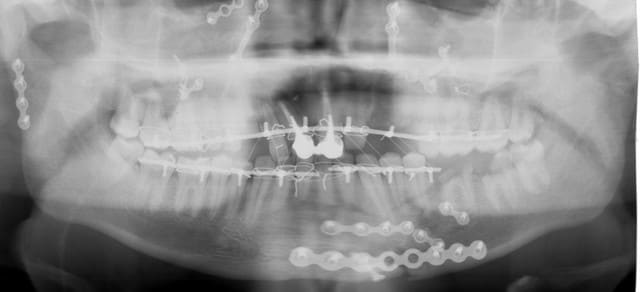

C'est parce que je vois les PM cassées en biseau que je pense à un AVP, avec un choc d'impact sous le menton. Déjà eu ce cas mais pas si amoché quand même...

Wahou! j'avais pas fais gaffe à la fracture du condyle droit en 3 morceaux... l'AVP se confirme... Ah moins que ce soit son mari avec une batte de base ball???

Pas de fracture au noveau de l'ATM droite???

Bon, elle ou il est pété(e) de tous les côtés. Mais l'os va sans doute se réparer. En tous cas, le point favorable, c'est que ce n'est pas un terrain carieux.

Donc, de la réhabilitation pure et dure sans risque de dégradation par la suite (sauf paro ?).

donc, effectivement, un gros choc avec fractures multiples. effectivement marco, c'est un cas long mais qui n'a rien de sorcier en soi, je l'ai posté parce qu'il étendu et impressionnant.

pour l'instant j'en suis à concevoir une approche, et je bute sur 36 et 37: endo + élongation + ccm, ou alors extraction? je crois que la 36 va sauter, mais 37 m'embête.

autre chose qui m'embête, c'est d'être obligé d'attendre la dépose des mini-plaques avant de pouvoir implanter 23 , 24 et 13.